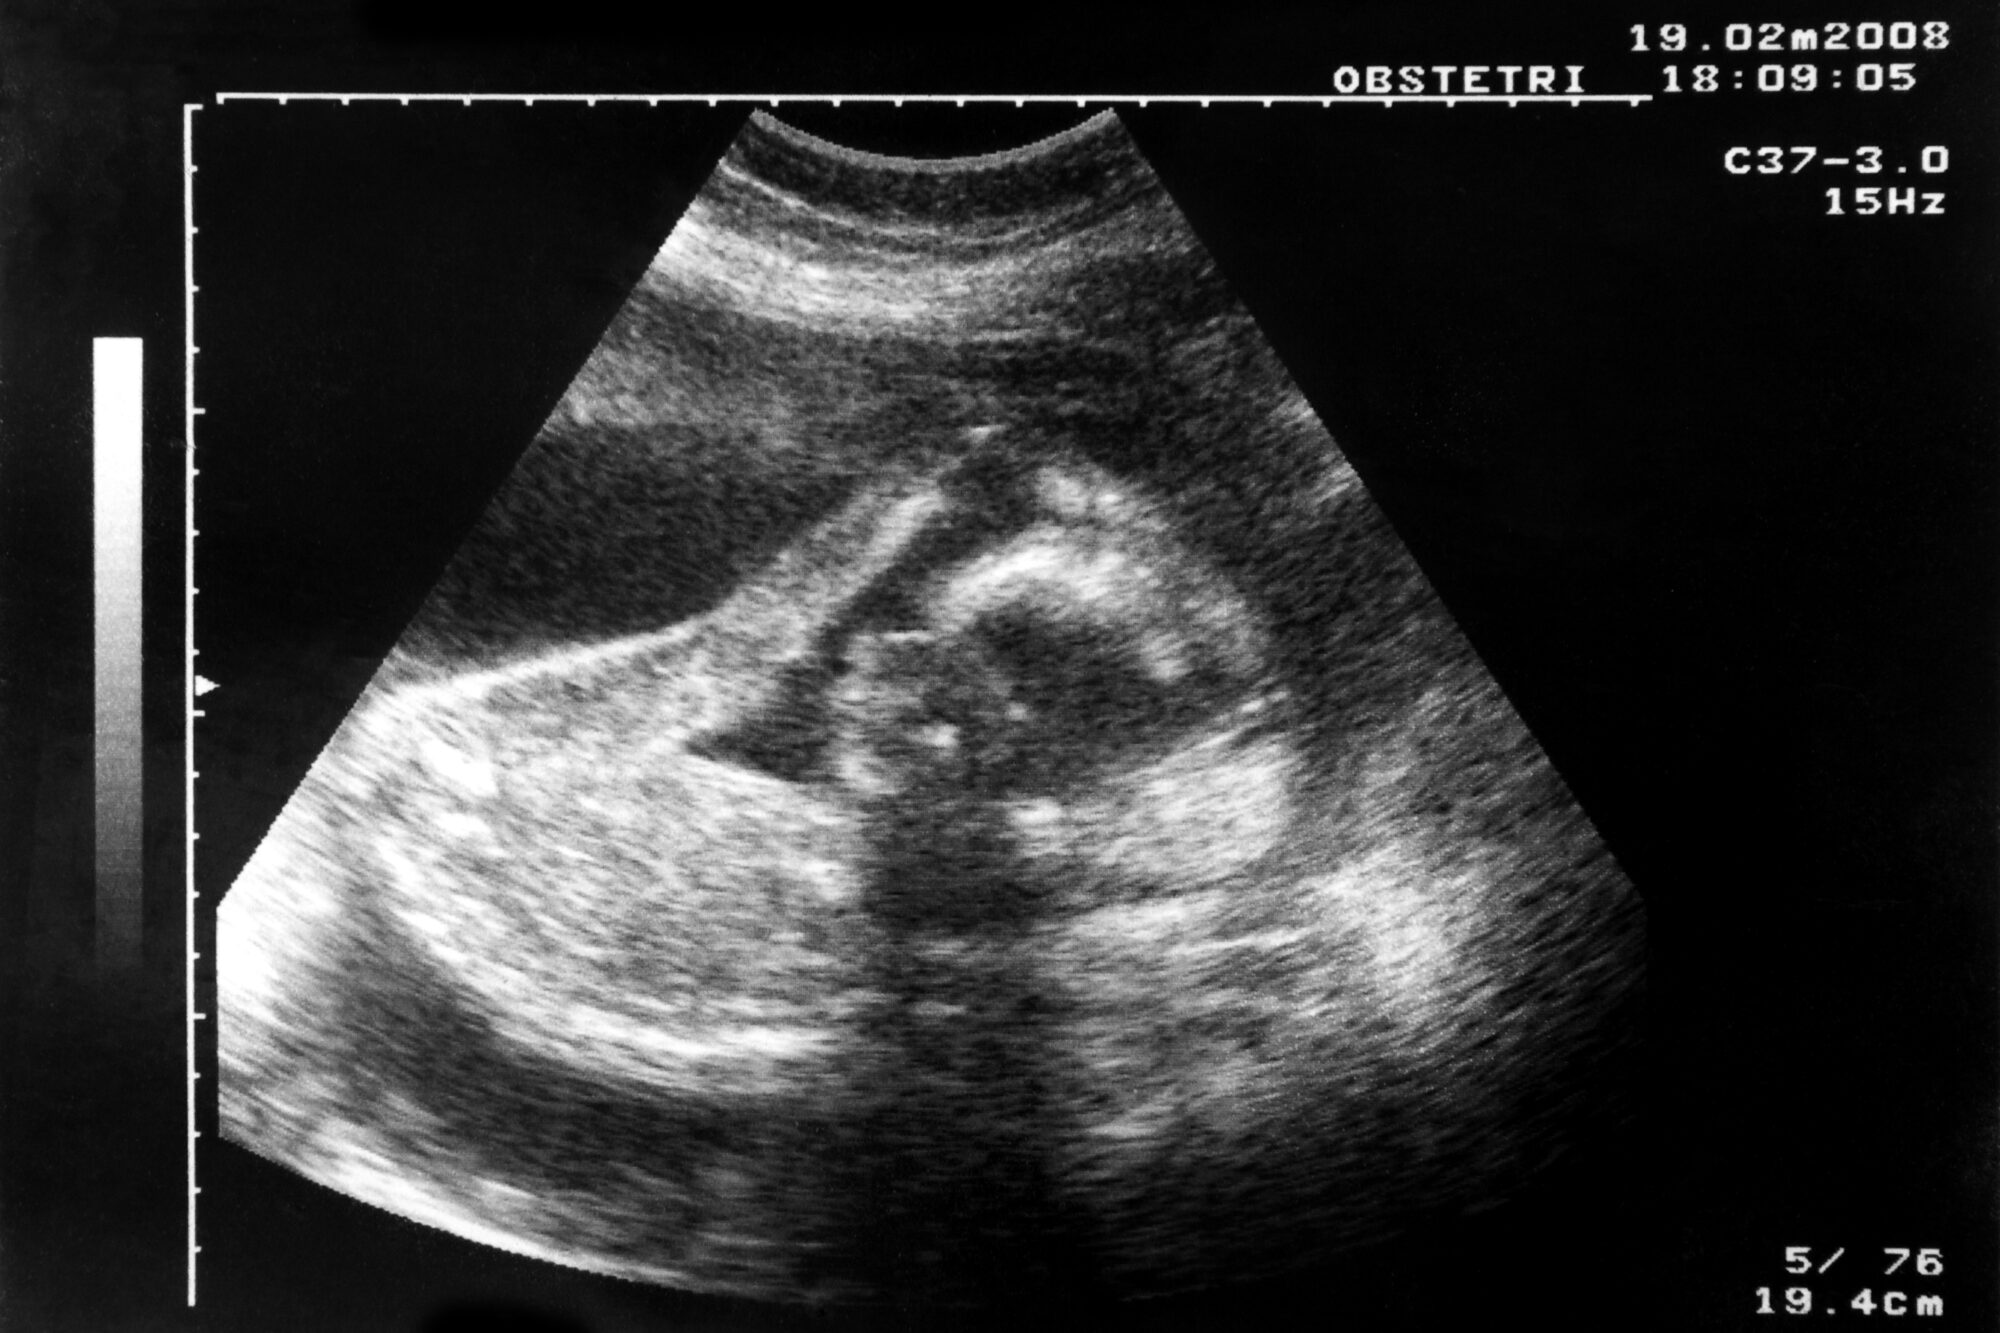

Det er fosterets helse som bekymrer gravide mest. Førsteamanuensis Bente Prytz Mjøland forteller at spesielt førstegangsfødende har et overforbruk av svangerskapskontroller sammenlignet med det som er anbefalt i basisprogrammet fra helsevesenet.. Illfoto: Colorbox